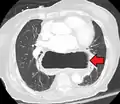

Four types of esophageal hiatal hernia are identified:[8]

Type I: A type I hernia, also known as a sliding hiatal hernia, occurs when part of the stomach slides up through the hiatal opening in the diaphragm.[9] There is a widening of the muscular hiatal tunnel and circumferential laxity of the phrenoesophageal ligament, allowing a portion of the gastric cardia to herniate upward into the posterior mediastinum. The clinical significance of type I hernias is in their association with reflux disease. Sliding hernias are the most common type and account for 95% of all hiatal hernias.[10] (C)

Type II: A type II hernia, also known as a paraesophageal or rolling hernia, occurs when the fundus and greater curvature of the stomach roll up through the diaphragm, forming a pocket alongside the esophagus.[9] It results from a localized defect in the phrenoesophageal ligament while the gastroesophageal junction remains fixed to the pre aortic fascia and the median arcuate ligament. The gastric fundus then serves as the leading point of herniation. Although type II hernias are associated with reflux disease, their primary clinical significance lies in the potential for mechanical complications. (D)

Type III: Type III hernias have elements of both types I and II hernias. With progressive enlargement of the hernia through the hiatus, the phrenoesophageal ligament stretches, displacing the gastroesophageal junction above the diaphragm, thereby adding a sliding element to the type II hernia.

Type IV: Type IV hiatus hernia is associated with a large defect in the phrenoesophageal ligament, allowing other organs, such as colon, spleen, pancreas and small intestine to enter the hernia sac.

The end stage of type I and type II hernias occurs when the whole stomach migrates up into the chest by rotating 180° around its longitudinal axis, with the cardia and pylorus as fixed points. In this situation the abnormality is usually referred to as an intrathoracic stomach.